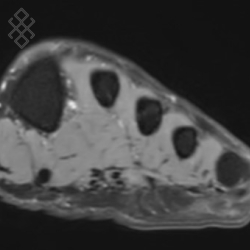

IRM du Pied/Avant-pied

Vous entrez dans l'aimant, ouvert des 2 côtés, les pieds en premier et allongé sur le dos avec les bras le long du corps. Pour recueillir le signal et construire les images, vous aurez le pied dans une antenne. Étant donné que cet examen est bruyant, vous aurez à votre disposition des tampons auriculaires pour atténuer le bruit de la machine.